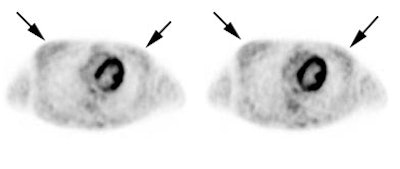

Vascular graft activity: The patient below had a prior graft repair of an ascending aortic aneurysm. Tracer uptake can be seen in the ascending aortic graft (black arrows). The patient also has a left upper lobe lung cancer (red arrows). |

|